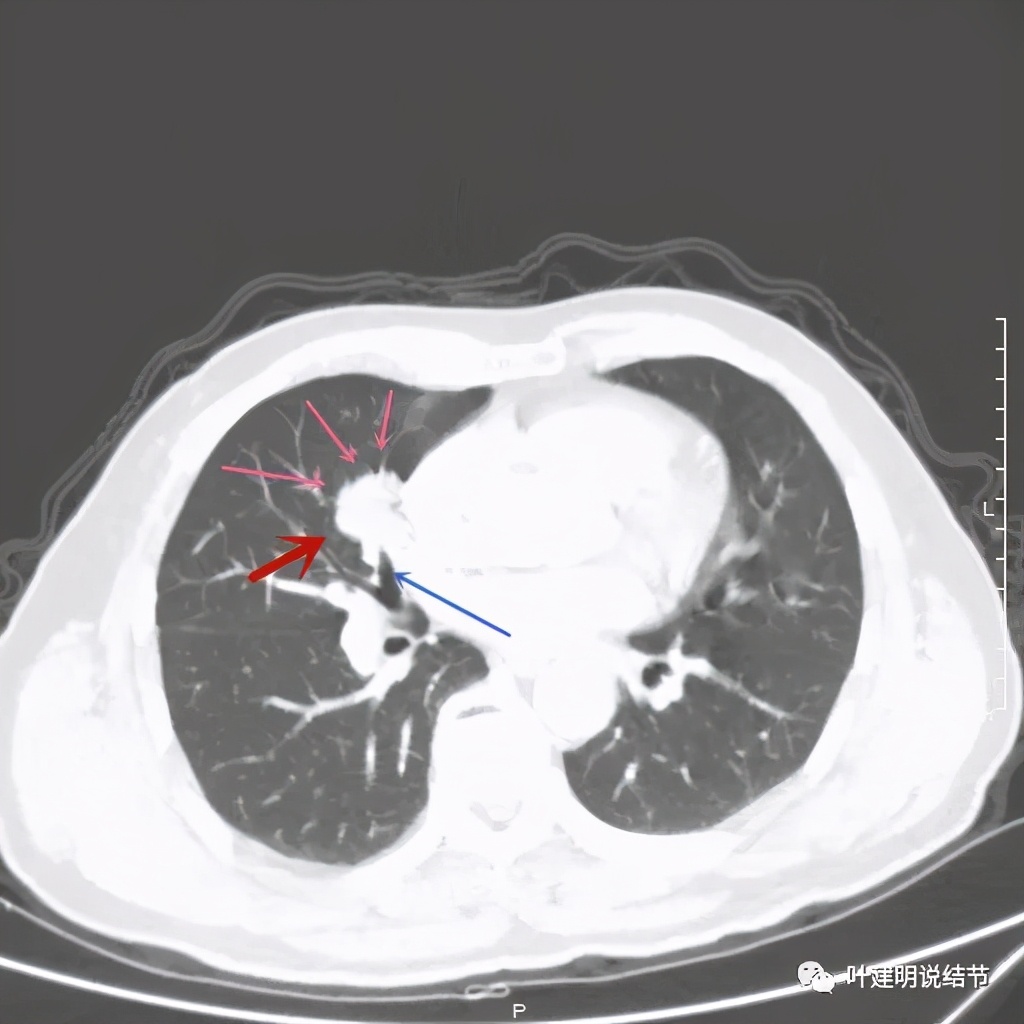

上图示病灶实性,且粉色箭头所示处边缘不平整,似细毛刺征(不太典型),蓝色箭头示像支气管截断(肿瘤堵塞的样子,但后文中有气管镜下未见异常,那么可能是角度的关系)

上图紫色箭头示浅分叶征明显,红色箭头示病灶牵拉胸膜(纵隔侧的胸膜)

上图绿色箭头示支气管通气征

仅从这几个层面,而且病灶周围清晰,没有渗出性改变或卫星灶,整体具有膨胀性、收缩力、分叶,基本上可以肯定是肺癌。结合纵隔淋巴结没有显著肿大,小细胞癌是不大像的,支气管镜未见气管内异常,所以鳞癌的可能性也小,腺癌最有可能!我与同事说,这个肯定要考虑肺癌,没有远处转移转移的话,可以手术的,也是要积极手术的。于是某A便办理了住院手续。住院后了解到,其实他早在今年3月初,即2个月前已经发现,而且当时就说考虑恶性,怎么又拖了2个月呢?